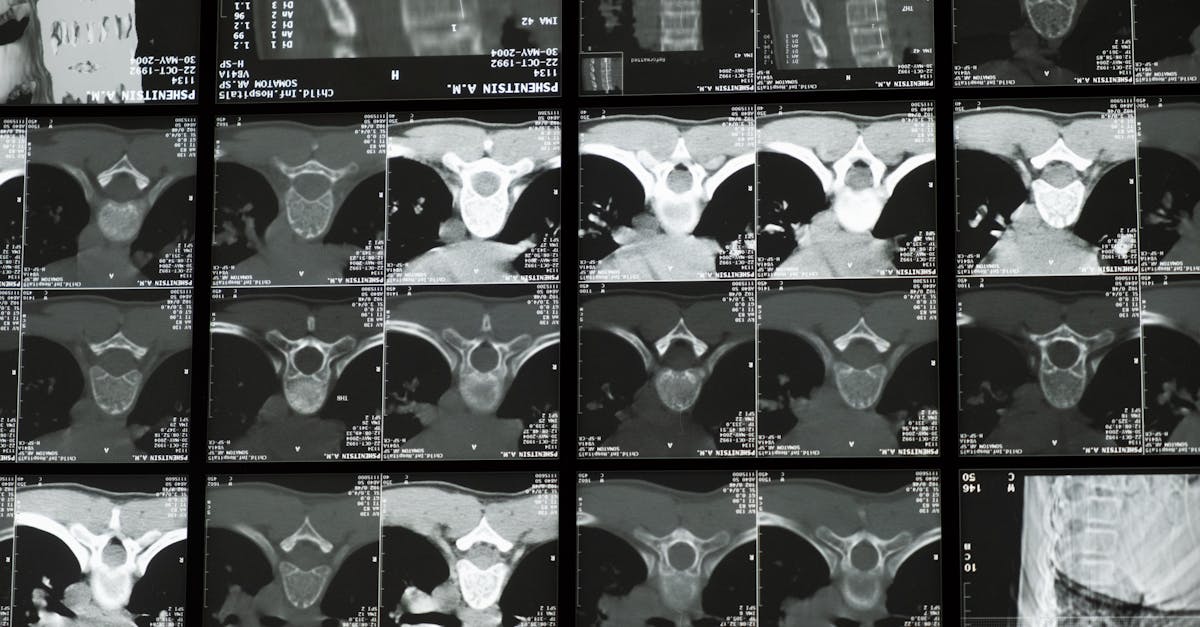

La décompression neurovertébrale utilise un appareil spécialisé pour exercer une traction contrôlée sur la colonne vertébrale. Cela crée un espace entre les vertèbres, réduisant ainsi la pression sur les nerfs et favorisant la circulation sanguine. Ce processus permet aux disques intervertébraux de se réhydrater et de se repositionner, ce qui est essentiel après une chirurgie.

La décompression neurovertébrale utilise des dispositifs spécialisés qui applient une traction contrôlée sur la colonne vertébrale. Cette technique crée un espace entre les vertèbres et permet aux disques intervertébraux de se réhydrater et de se repositionner, réduisant ainsi la pression sur les nerfs adjacents. Lorsque cette pression diminue, les symptômes associés à la douleur et à l’inflammation s’estompent, améliorant ainsi la mobilité et la posture du patient.

Dans le cadre de cette thérapie, des appareils spécialisés, souvent utilisés sur une table de traction, exercent une pression contrôlée sur la colonne vertébrale, permettant de réduire la tension sur les disques intervertébraux. Cette approche peut s’intégrer efficacement dans le parcours de soins post-opératoires, offrant un soutien nécessaire pour restaurer une posture correcte et améliorer la fonction musculaire. Grâce à des séances planifiées et à une évaluation régulière des progrès, les thérapeutes peuvent ajuster les traitements pour s’adapter aux besoins spécifiques de chaque patient.